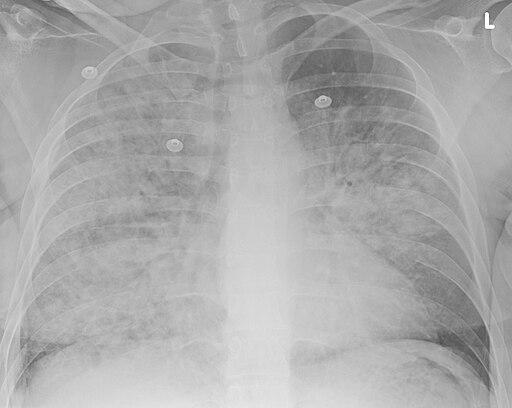

Aspirationspneumonie

Doc James, CC BY-SA 4.0, über Wikimedia Commons

Eine Röntgenaufnahme der Brust.